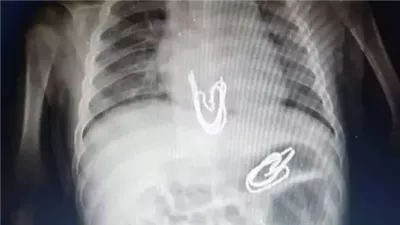

نجاح طبي بسوهاج الجامعي.. استخراج دبوس من معدة طفل دون جراحة

شهد مستشفى سوهاج الجامعي إنجازًا طبيًا جديدًا يُضاف إلى سجل نجاحاته في رعاية الأطفال، حيث تمكن فريق طبي متخصص من وحدة أمراض الجهاز الهضمي والكبد ومناظير الأطفال بقسم طب الأطفال من إجراء تدخل دقيق لاستخراج جسم غريب من معدة طفل يبلغ من العمر 4 سنوات، باستخدام منظار معدة مخصص للأطفال، دون الحاجة إلى تدخل جراحي، ووسط إجراءات دقيقة وآمنة.